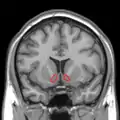

Nucleus accumbens

Approximate location of the nucleus accumbens in the brain